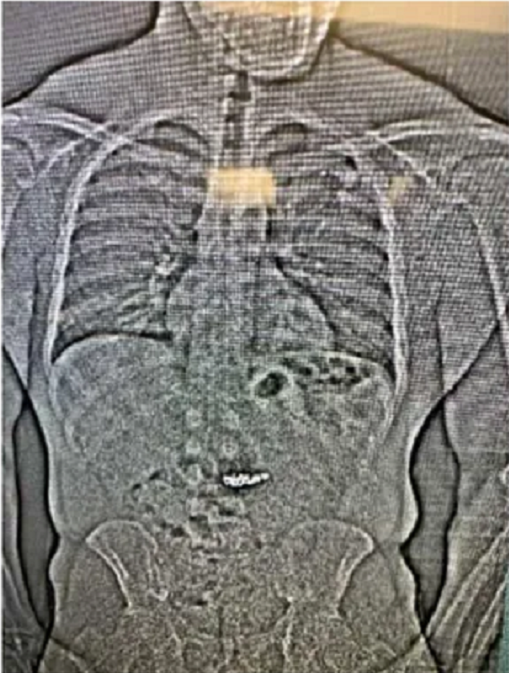

| Ảnh chụp X-quang cho thấy vật thể lạ trong đường tiêu hoá của tên trộm. Ảnh: Fox35. |